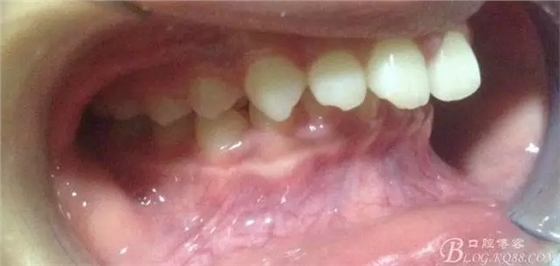

佩戴三個(gè)月的FR2, 效果奇佳!前牙基本達(dá)到淺覆蓋,淺覆合!接下來進(jìn)入二期直絲弓固定正畸,排齊階段!

接下來盡管配合些雙側(cè)后牙對(duì)角牽引,咬合關(guān)系依,不盡人意。